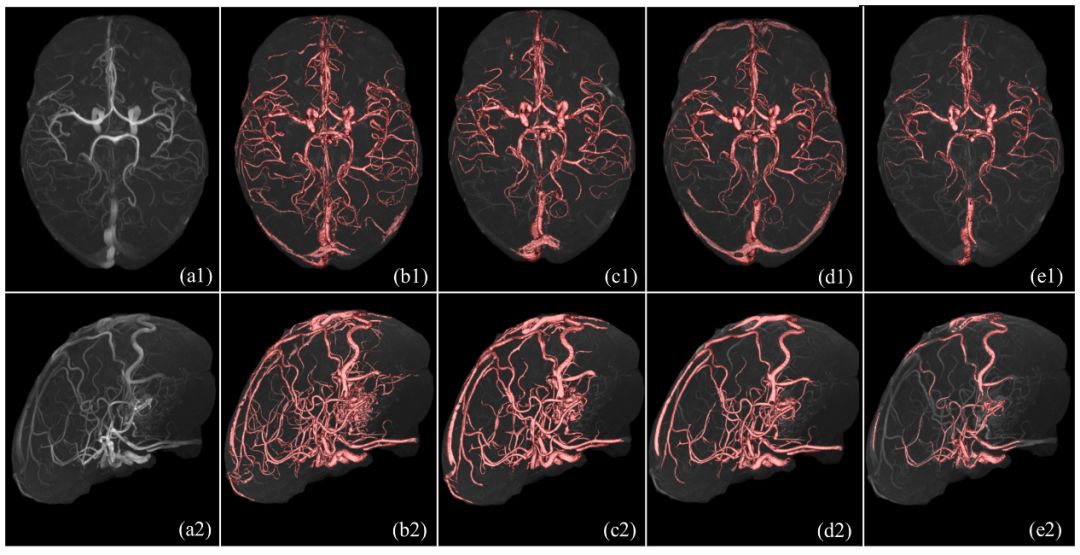

图三: 实验结果(一种新颖的设备无关的TOF-MRA数据分割的统计学建模方法)

现有的各类脑磁共振血管分割方法依赖于特定MR成像设备或特定数据集,基于模型驱动的血管分割方法通常不能完整地提取脑血管网络并且存在过分割现象,基于深度学习的方法受限于海量数据标注问题。上述两篇论文分别提出了两种鲁棒的统计学方法,实现任意磁共振设备型号下的TOF-MRA三维数据的全脑血管拓扑结构精确提取,如图一、二、三,该研究可以对深度学习方法提供血管数据的自动标注工具;在特定磁共振设备下,实现基于三维TOF-MRA和MR-T1数据的完整脑动脉和脑静脉结构的精确分割,如图四(f)。上述成果对于脑血管的自动标注、分割、临床可视化具有重要现实意义。

图四:由左至右为十套脑磁共振血管造影数据的分割结果:(a)原始TOF-MRA造影数据的最大密度投影视图;(b-e):4种对比方法;(f):本文所提方法;(g-h):动静脉分离结果